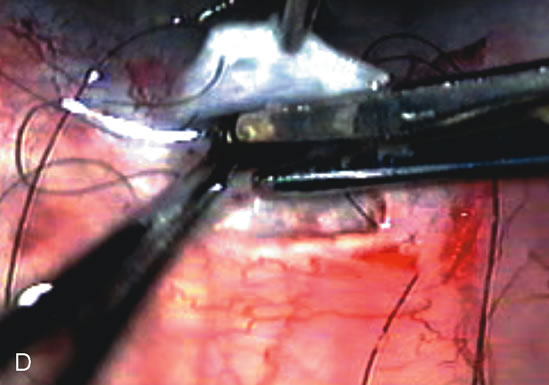

Fig. 7. Phacotrabeculectomy adjacent to a failed filter in cataractous eye. The ability to combine small-incision cataract extraction with trabeculectomy all through the same incision adjacent to the failed filter allows the surgeon to work in a familiar superior area. Avoiding incisions into the existing bleb decreases conjunctival buttonholes, hypotony, operating room time, and subconjunctival bleeding. A. Appearance of failed bleb with exposure of superior temporal quadrant gained with a corneal traction suture. B. Prepare a limbus-based conjunctival flap and a scleral flap. C. This bleb is at high risk to fail again justifying the need for MMC, 0.2 mg/cc applied on a pledget for 4 minutes. D. Insert the keratome and perform phacotrabeculectomy in the usual fashion.